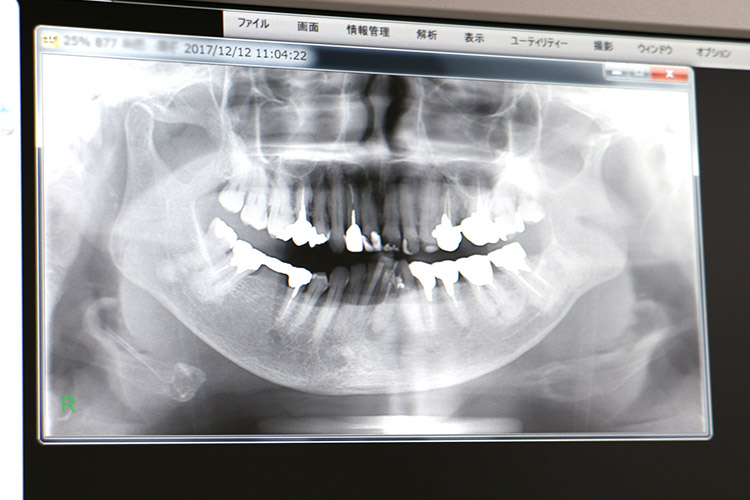

■ 検査 33,000円(税込)

治療の必要性があると判断した場合には、お口の型取り、歯やお顔の形態を診断するためのレントゲン撮影(3~5種)、お口とお顔の写真撮影等をさせていただきます。大人の方は顎の動きを調べるための「顎運動機能検査」を追加でさせていただくことがあります。 別途16,500円(税込)